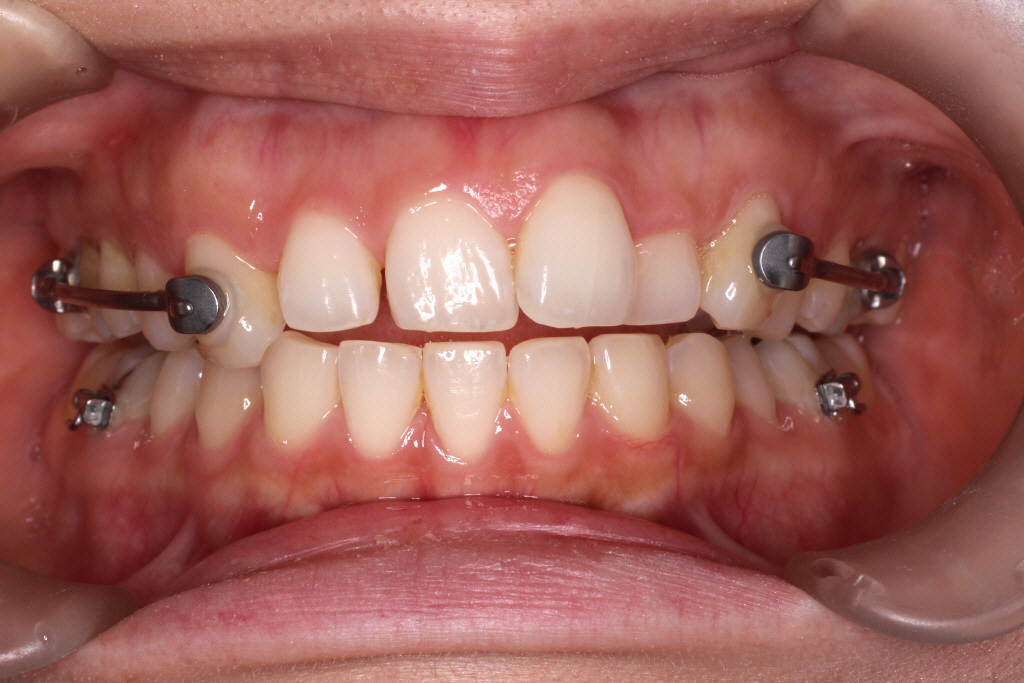

こちらがカリエールモーション終了時の口腔内写真です。

正中のずれが治ってきているのと、

上の前歯のがたつきが少しよくなっているのが分かります。

また、右の奥歯が1歯分後ろにさがっている事が分かります。

この状態まできたら、カリエールモーションの装置をはずし

今度はインビザラインにて治療を行っていきます。